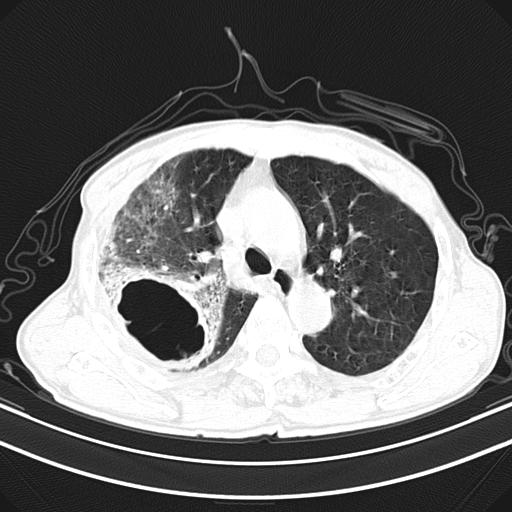

抗炎治疗10天后复查

抗炎治疗10天后复查:右上肺模糊阴影明显减少。